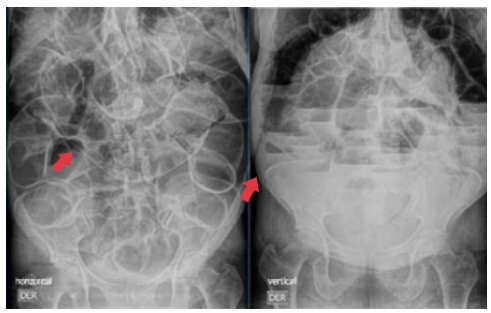

Al ingreso, a la paciente se le realiza, por un lado, radiografía posteroanterior y lateral de tórax con hallazgo incidental de neumatosis intestinal en la flexura esplénica del colon, asociado a la sobredistensión de las asas intestinales y elevación del hemidiafragma derecho e izquierdo, con evidencia de aire subdiafragmático bilateral compatible con neumoperitoneo (Figura 2), y, por el otro, radiografía de abdomen simple, que muestra sobredistensión de asas intestinales, formación de niveles hidroaéreos y ausencia de gas distal (Figura 3).

Radiografía posteroanterior y lateral de tórax. → presencia de aire intraluminal y extraluminal como signo de neumoperitoneo.

Figura 2: Radiografía posteroanterior y lateral de tórax. → presencia de aire intraluminal y extraluminal como signo de neumoperitoneo.

Fuente: Documento obtenido durante la realización del estudio.